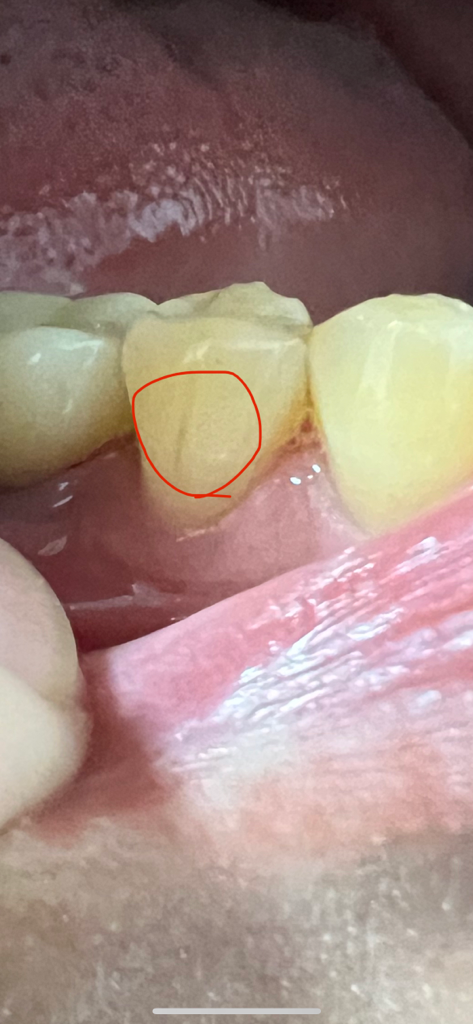

치아 표면에 검은선이 생겼어요..

검은선 주변으로 단차가 잇다거나

금이 가서 손톱으로 느꼇을때 단차가 느껴지는건 없는거같아요 . 6개월마다 치과을 가구요 시리거나 아프거나 그런건 전혀 없습니다.

단순 craze line인가요?

단차가 없다면 단순 착색일수도 있을것 같습니다.

아마도 치아에 실금이 간부위에 변색이 된거 같습니다. 크게 문제가 잇는건 아니니 걱정하지 않으셔도 됩니다.

금이 가있는 것으로 보이며 당장 증상이 없으시면 그대로 두셔도 괜찮습니다.

실금일 가능성이 있어 보이나 해당 부위 정도라면 파절 되었을 가능성이 있습니다. 즉 단차가 느껴지지 않더라도 내부에서 금이 간 경우도 있을 수 있습니다. 보통 증상 초기에는 통증이나 불편감이 나타나지 않을 수 있으니 주기적으로 치과 방문 후 검진을 하거나 dental-CT 등을 찍어보는 것을 권해드립니다.